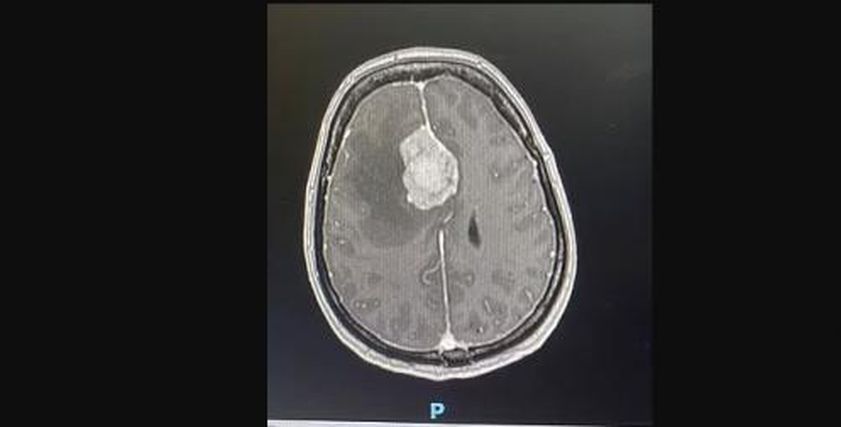

وقالت صحيفة «ديلي ميل» البريطانية، إنه في مارس 2023، كشفت الفحوصات عن السبب الحقيقي للأعراض، وهو إصابة السيدة وهي سباحة سابقة، بورم سحائي (مينينجيومًا) – وهو ورم ينمو في الأغشية المحيطة بالدماغ.

الورم السحائي يبدأ في طبقة الأنسجة المحيطة بالدماغ والحبل الشوكي، وتُعرف بـالسحايا، وعادةً ما ينمو الورم السحائي ببطء، ولهذا قد لا تكون الأعراض واضحة في البداية، لكن مع نموه، يمكن أن يضغط على المناطق القريبة من الدماغ، ما يؤدي إلى أعراض ذكرتها منظمة «الصحة العالمية»، وموقع «webmd» الطبي، كالتالي: